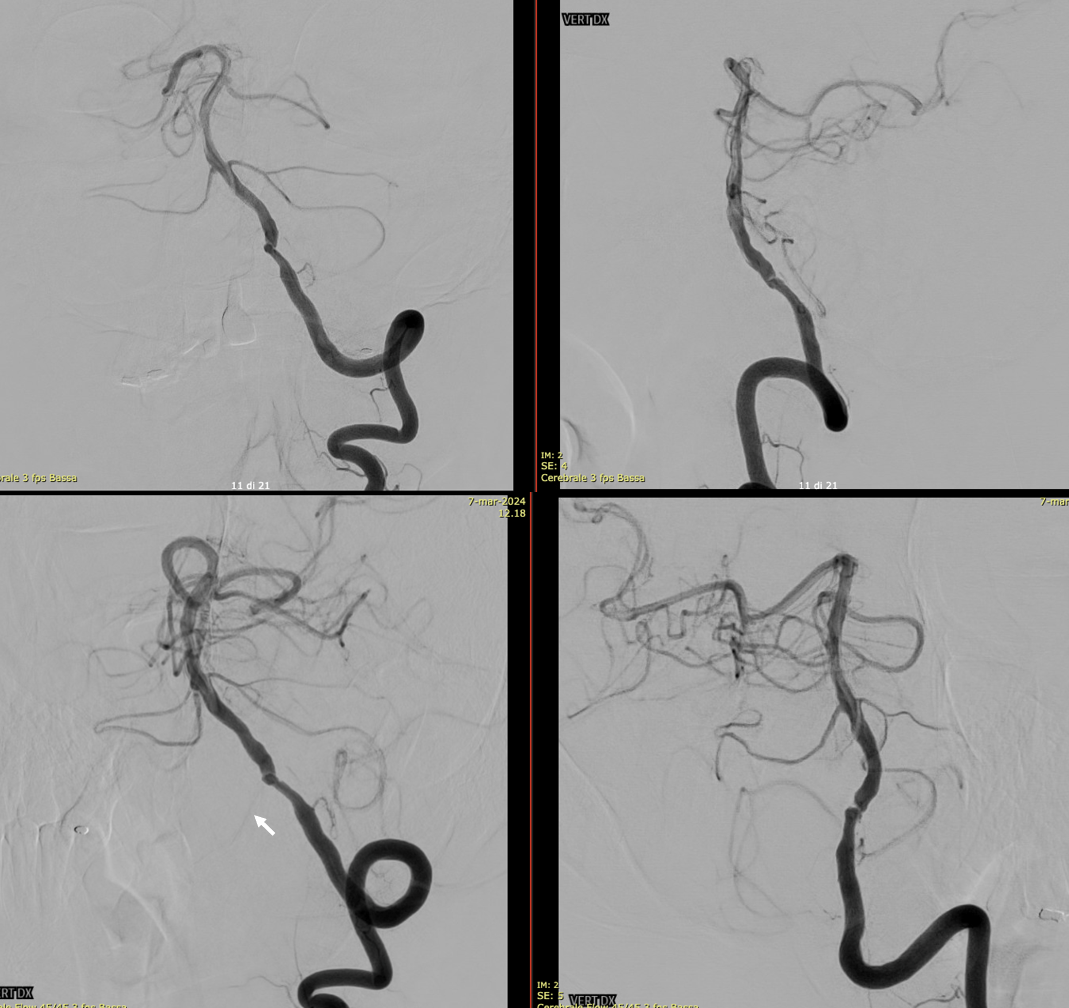

Diagnostic DSA with left vert injection. We can see an irregular stenosis of the pre-junctional vert, AICA-PICA and a small lateral spinal artery (arrow) originating below the stenosis.